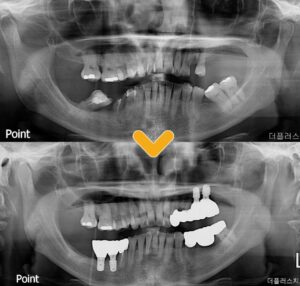

환자분의 현재 상태에서

맞출 수 있는 방향으로 임플란트 식립과

함께 브릿지 치료를 진행하였습니다.

많이 쓰러져 있던 치아들도

최대한 살릴 수 있는 방향으로 브릿지를 걸어

관리해서 쓸 수 있을 만큼 써보자고

상담하며 진행하였기 때문에